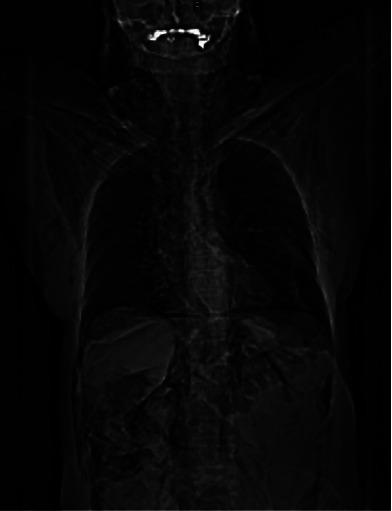

A 71-year-old female that went to the emergency room due to acute generalized abdominal colic spasm pain with a duration of 7 hours, associated with significant abdominal distension, malaise, diaphoresis, progressive dyspnea, and massive subcutaneous emphysema that developed after performing panendoscopy and colonoscopy for diverticulosis follow-up. An abdominal CT scan with double contrast was performed, reporting suggestive data of hollow viscus perforation, pneumoperitoneum, pneumomediastinum, pneumothorax, and massive subcutaneous emphysema in the thorax, neck, and skull base. She underwent an exploratory laparotomy finding a perforation in the sigmoid for which sigmoidectomy was performed, and for the pneumothorax and pneumomediastinum, endopleural tubes were placed in both hemithoraxes. The massive subcutaneous emphysema subsided with observation and oxygen.

一名71岁女性因急性全身性腹部绞痛痉挛性疼痛持续7小时前往急诊室,伴有明显腹胀、不适、出汗、进行性呼吸困难以及在为憩室病进行全身内镜检查和结肠镜检查后出现的大量皮下气肿。进行了腹部双重对比CT扫描,报告显示有中空脏器穿孔、气腹、纵隔气肿、气胸以及胸部、颈部和颅底大量皮下气肿的提示性数据。她接受了剖腹探查术,发现乙状结肠穿孔并进行了乙状结肠切除术,对于气胸和纵隔气肿,在双侧胸腔放置了胸膜内导管。大量皮下气肿通过观察和吸氧消退。